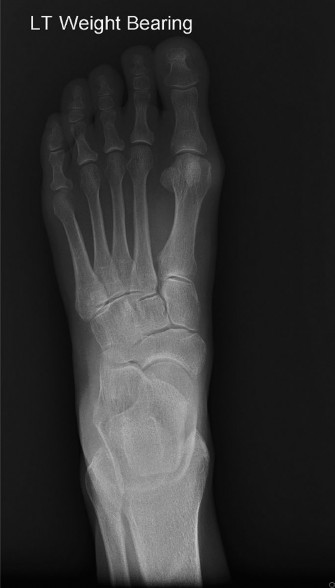

• Weight-Bearing Radiographs (AP, Lateral, Oblique Foot/Ankle): Crucial for bony assessment.

• Identify accessory navicular (Type II often seen as a separate ossicle).

• Assess for other bony abnormalities (osteophytes, tarsal coalition, stress fractures).

• Evaluate the medial longitudinal arch height and alignment (Meary's angle, Talo-first metatarsal angle on lateral view; Talo-navicular coverage angle on AP view) for PTTD assessment.